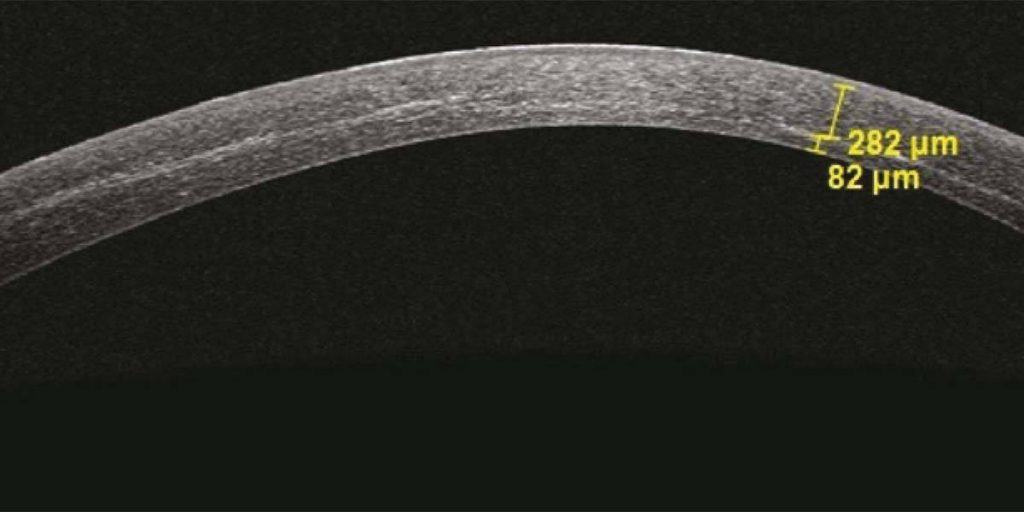

Mas com o CXL, as córneas finas - frequentemente as córneas que mais necessitam de tratamento - podem causar grandes dores de cabeça. Há uma boa razão para que o protocolo padrão de Dresden para CXL seja limitado a córneas com uma espessura >400 µm. As córneas mais finas correm o risco de a luz UV penetrar mais profundamente e danificar as células endoteliais na base da córnea. Como estas células não se podem regenerar, os cirurgiões que realizam o CXL tiveram de encontrar formas de tornar estas córneas finas temporariamente mais espessas (por exemplo, inchando a córnea com riboflavina hipo-osmolar ou aplicando uma lente de contacto na córnea). Estes métodos complicam certamente o procedimento e acrescentam também um elemento de incerteza. Não tem de ser assim.

O nosso trabalho de investigação permitiu-nos construir um modelo validado da forma como os quatro componentes principais da técnica CXL (energia UV, tempo de irradiação UV, concentração de riboflavina e pressão de oxigénio) interagem para endurecer a córnea. Isto permite-nos determinar não só o efeito de endurecimento de qualquer combinação dos componentes principais do CXL, mas também a profundidade dos efeitos do CXL utilizando irradiação UV personalizada. Por outras palavras, pode ser utilizado um perfil de iluminação UV personalizado - com um tempo de irradiação mais curto - para tratar córneas mais finas, adaptado ao olho de cada doente, simplificando e acelerando o tratamento de córneas finas com CXL.